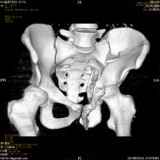

Повреждение вертлужной впадины 2,5 мес. |

Уважаемые коллеги! Хотелось бы услышать совет по тактике лечения представлленого больного.Поступил после лечения в одном изотделений области. Травма 2,5 месяца назад. После выведенияиз шока был произведен остеосинтез перелома бедра, предплечья, до перевода к нам проводилосьвытяжение по оси шейки бедра за стержень, введенный в большой вертел. На сегодня деформацияригидна, клинически мобильности не определяется. Заранее признателен. P.S. Данный вид травм не включен в перечень "высокотехнологичных операций", направить длялечения по квотам Минздрава очень сложно.

Это обзорные и косые снимки

Привет, Леонид. Оскольчатый высокий двухколонный перелом в такие сроки трогать не надо, т.к. это про такие переломы сказано: "кто с ножом на Ж. пойдет тот в ней и останется...".